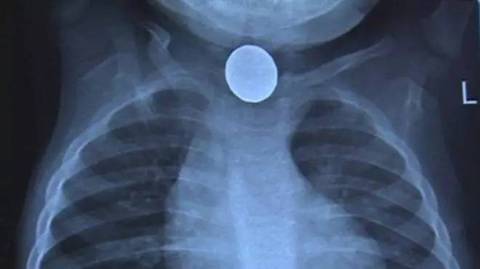

5岁女孩误吞纽扣电池食道被烧穿1个洞

在这宗意外中,虽然加拉赫反应及时,但拉蒂莎的食道还是被烧穿了个洞。

儿童误吞之后,锂电池会依附在食管上,毒物泄漏后灼伤食道导致食道穿孔。如果停留时间长,毒物还会下行到肺部,造成进一步伤害。